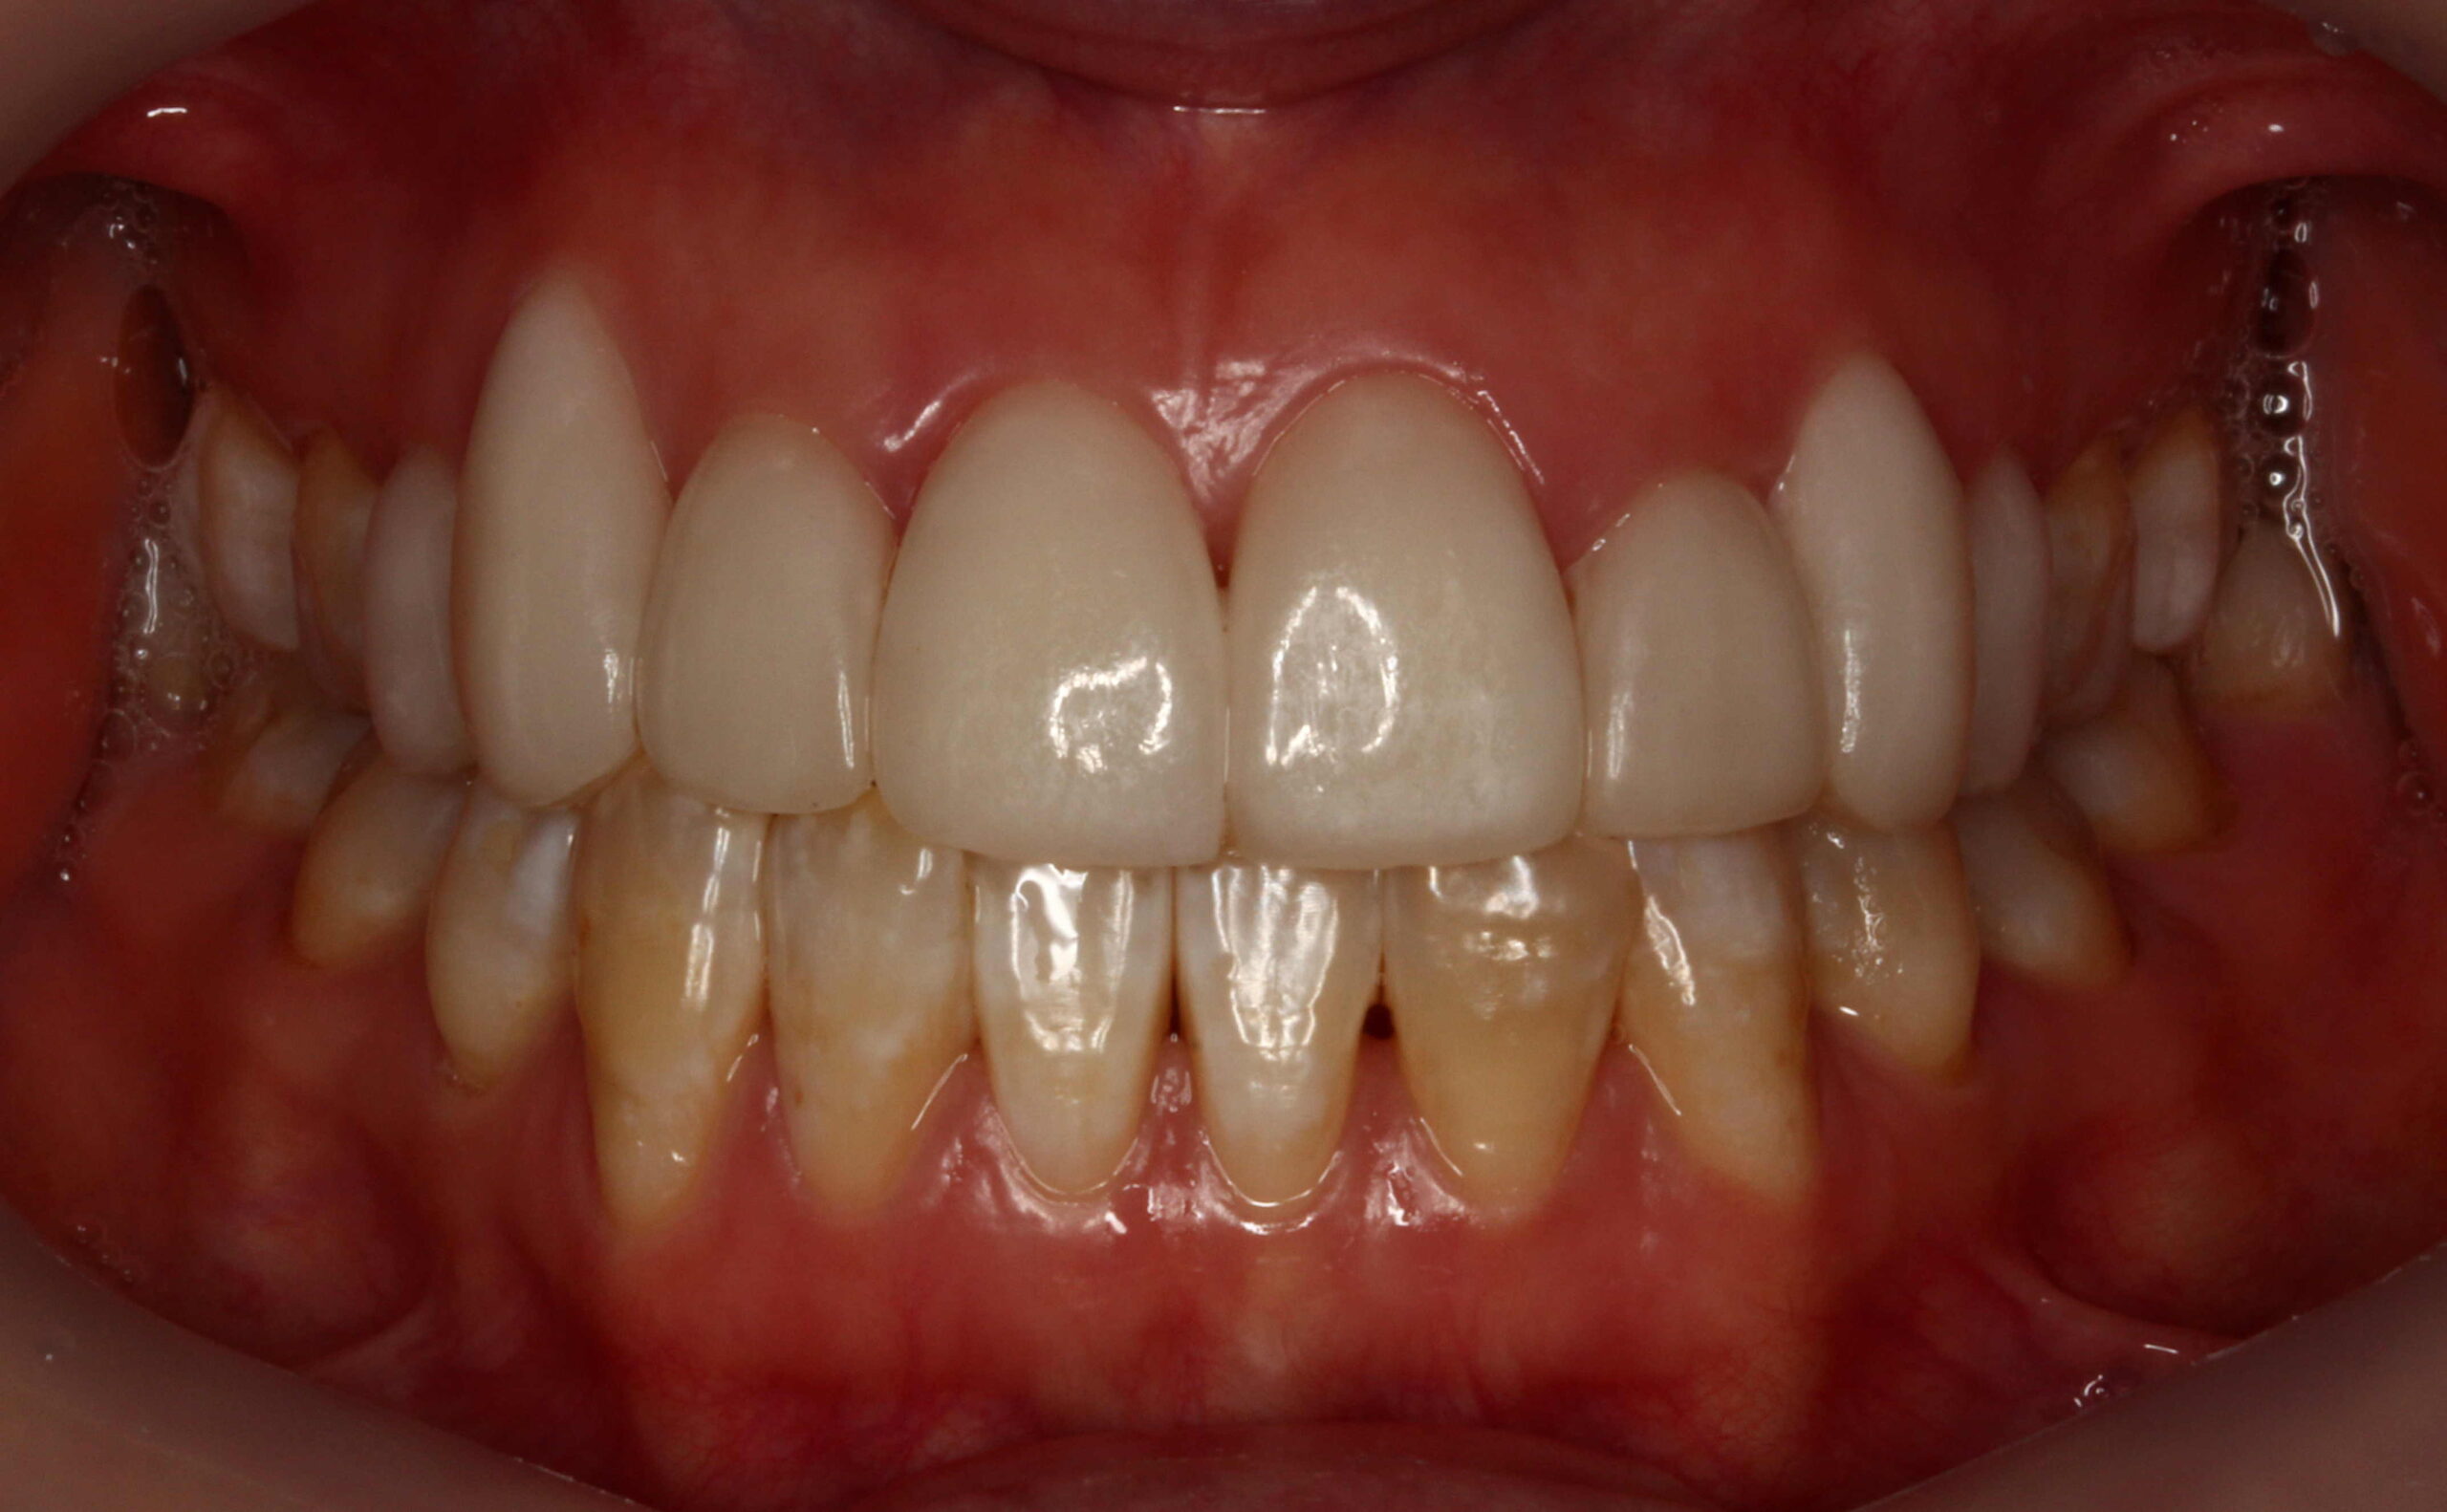

前歯6本の削らないラミネートベニア症例です。

すきっ歯を直し、白く理想的な歯並びにしたいとのことです。

すきっ歯の改善は削らないラミネートベニアが最も得意とする症例の1つです。

歯と歯の隙間をなくして、スマイルラインに沿ったキレイな仕上がりになりました。

削らないラミネートベニアの色は自然で明るい白をご希望で、お顔の印象も明るくなりました。

天然歯を削ることのない新しいセラミックの審美歯科です。